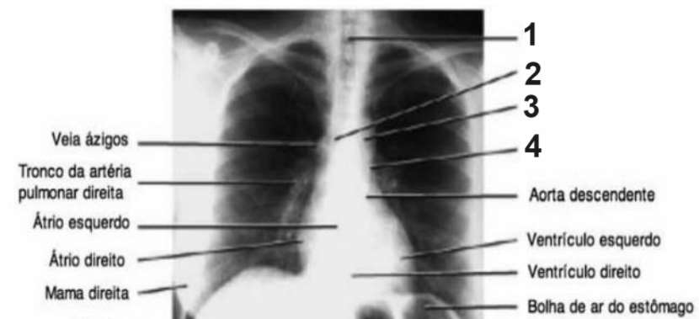

Analise a imagem abaixo.

O número 1 acima indica o(a):